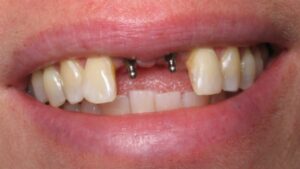

جماليات زراعة الأسنان

يتم تخطيط وتنفيذ إجراء زراعة الأسنان بعناية لضمان أن ترميم الأسنان يبدو طبيعيًا في الشكل واللون والمكان. نعطي الأولوية لراحة مرضانا بالإضافة إلى الجماليات. وهذا يتطلب مزيجًا مثاليًا من العبقرية الفنية والجراحية. لذلك ، يتم تنفيذ جميع حالات الزرع لدينا من قبل فريق من أطباء الأسنان التجميليين وأخصائي زراعة الأسنان.